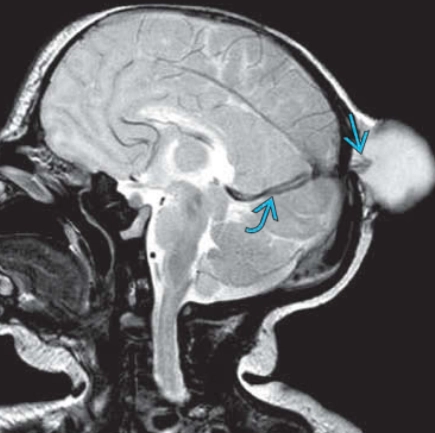

• Thoát vị não-màng não đỉnh dạng thoái triển (Atretic parietal cephaloceles)

Thoát vị não-màng não đỉnh dạng thoái triển (Atretic parietal cephaloceles)

• Thoát vị màng não thoái triển thai nhi (Atretic cephalocele)